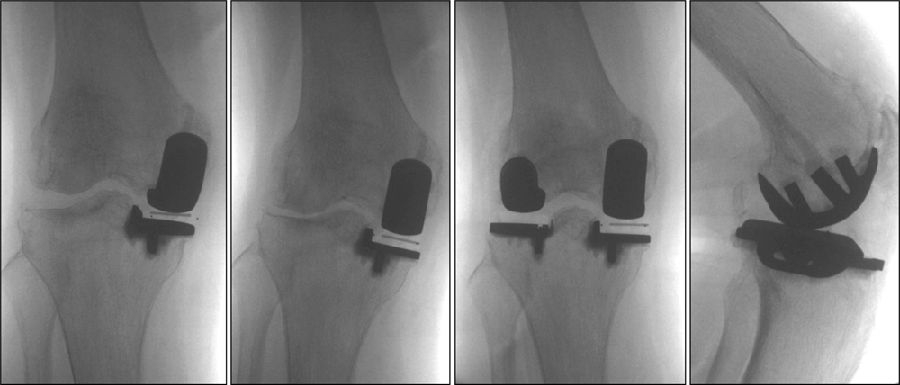

理想假体位置 A.股骨假体 胫骨假体中心线一致;B.股骨假体固定栓与后侧皮质呈35-40°

理想假体位置即前缘平稳过渡,后缘包容很好且不超出。

术后透视。A.正位B.侧位

术后1周X-ray片